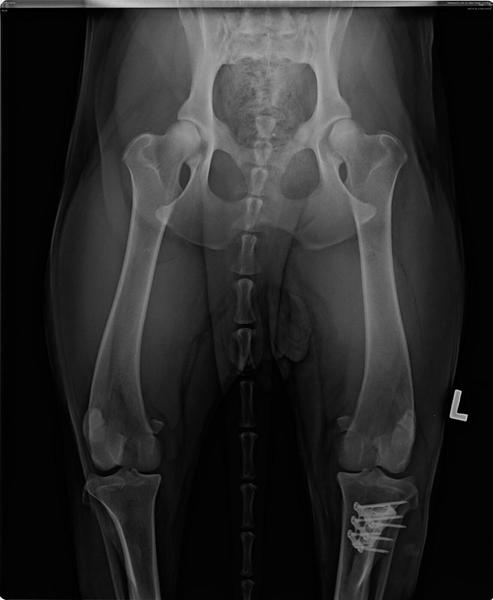

Das Implantat, das die inneren Kreuzbänder ersetzt, ist gut in Amélies Kmochen eingewachsen. Man merkt, dass es ihr langsam besser geht, die "Renneinheiten" werden wieder länger und ausgedehnter!

Inwzischen sind 8 Wochen seit Amélies Kreuzband-Op vergangen, und so langsam können wir mit Muskelaufbautraining beginnen. Unsere Spazierrunden werden sukkzessive länger - auch wenn Amélie noch an der Leine bleiben muss. Auch das Treppensteigen klappt inzwischen schon ganz gut. Heute waren wir alle zusammen unterwegs, und Zeit für einige Bilder blieb auch noch.  Als letzte hat nun auch Amélie ihren Sommerhaarschnitt erhalten. Dieses Gesicht ist einfach zum Verlieben!